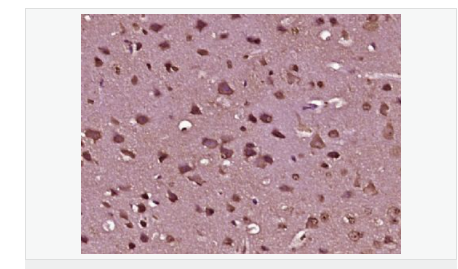

產(chǎn)品介紹The protein encoded by this gene belongs to the B-cell CLL/lymphoma 2 and adenovirus E1B 19 kDa interacting family, whose members play roles in many cellular processes including apotosis, cell transformation, and synaptic function. Several functions for this protein have been demonstrated including suppression of Ras homolog family member A activity, which results in reduced stress fiber formation and suppression of oncogenic cellular transformation. A high molecular weight isoform of this protein has also been shown to colocalize with Adaptor protein complex 2, beta-Adaptin and endodermal markers, suggesting an involvement in post-endocytic trafficking. In prostate cancer cells, this gene acts as a tumor suppressor and its expression is regulated by prostate cancer antigen 3, a non-protein coding gene on the opposite DNA strand in an intron of this gene. Prostate cancer antigen 3 regulates levels of this gene through formation of a double-stranded RNA that undergoes adenosine deaminase actin on RNA-dependent adenosine-to-inosine RNA editing. Alternative splicing results in multiple transcript variants. [provided by RefSeq, Jul 2015]

image.png